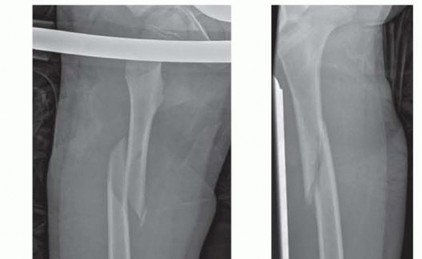

Chapter 32 Intramedullary Nailing of the Mature Tibia Mark A. Lee Jonathan G. Eastman Brett Crist DEFINITION …